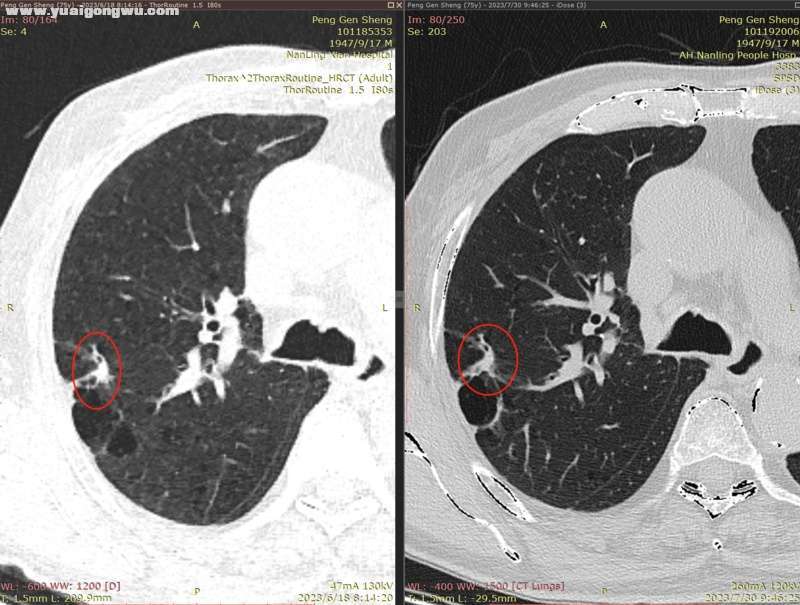

6月3日~7月29日,单用安罗替尼12mg(3周期),6月18日CT显示左肺主病灶稍缩(主病灶62mmx57mm);因近期有一点点吸不上气的感觉(吸氧后有缓解,其他身体体征正常,体感良好),7月30日CT显示左肺主病灶稍增大(主病灶68mmx62mm)。- L* L' w9 C: J7 b

影像科医生将7月30日的胸部CT,和6月18日的胸部CT电子影像对比分析如下:

2、右肺多发小结节,前面两枚之前重点关注的结节(有时变大有时变小),这次复查略微变小(图2~5;+ }% G% E$ F0 e  U; {- |' V' B

3、右肺中叶实变区域,体积略变小(图6);- z3 W  \% n% e

4、纵膈小淋巴结、肺部炎症情况基本没有变化。% y' R# g! n. ^# F) M8 n

* R5 w. e) k/ [9 Y( L' s' h* x* n7 d        以下为近两次CT影像的对比分析。7 Z8 B" @7 n7 B# ?+ K" ?( E( {) v